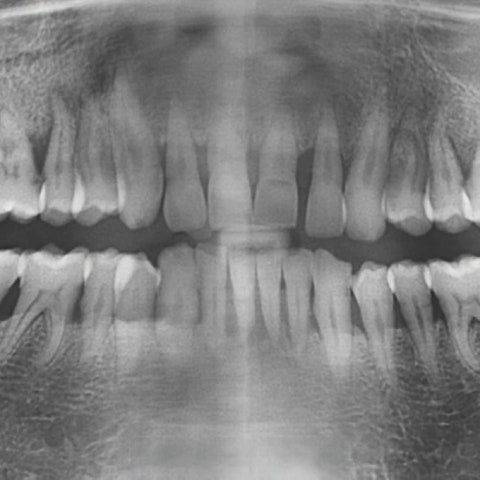

그리고 근래에 개원한 치과중에 드물게 임상경력이 20년차이며, 치아교정뿐 아니라 임플란트,

충치치료등 전반적인 진료를 모두하고 있습니다.